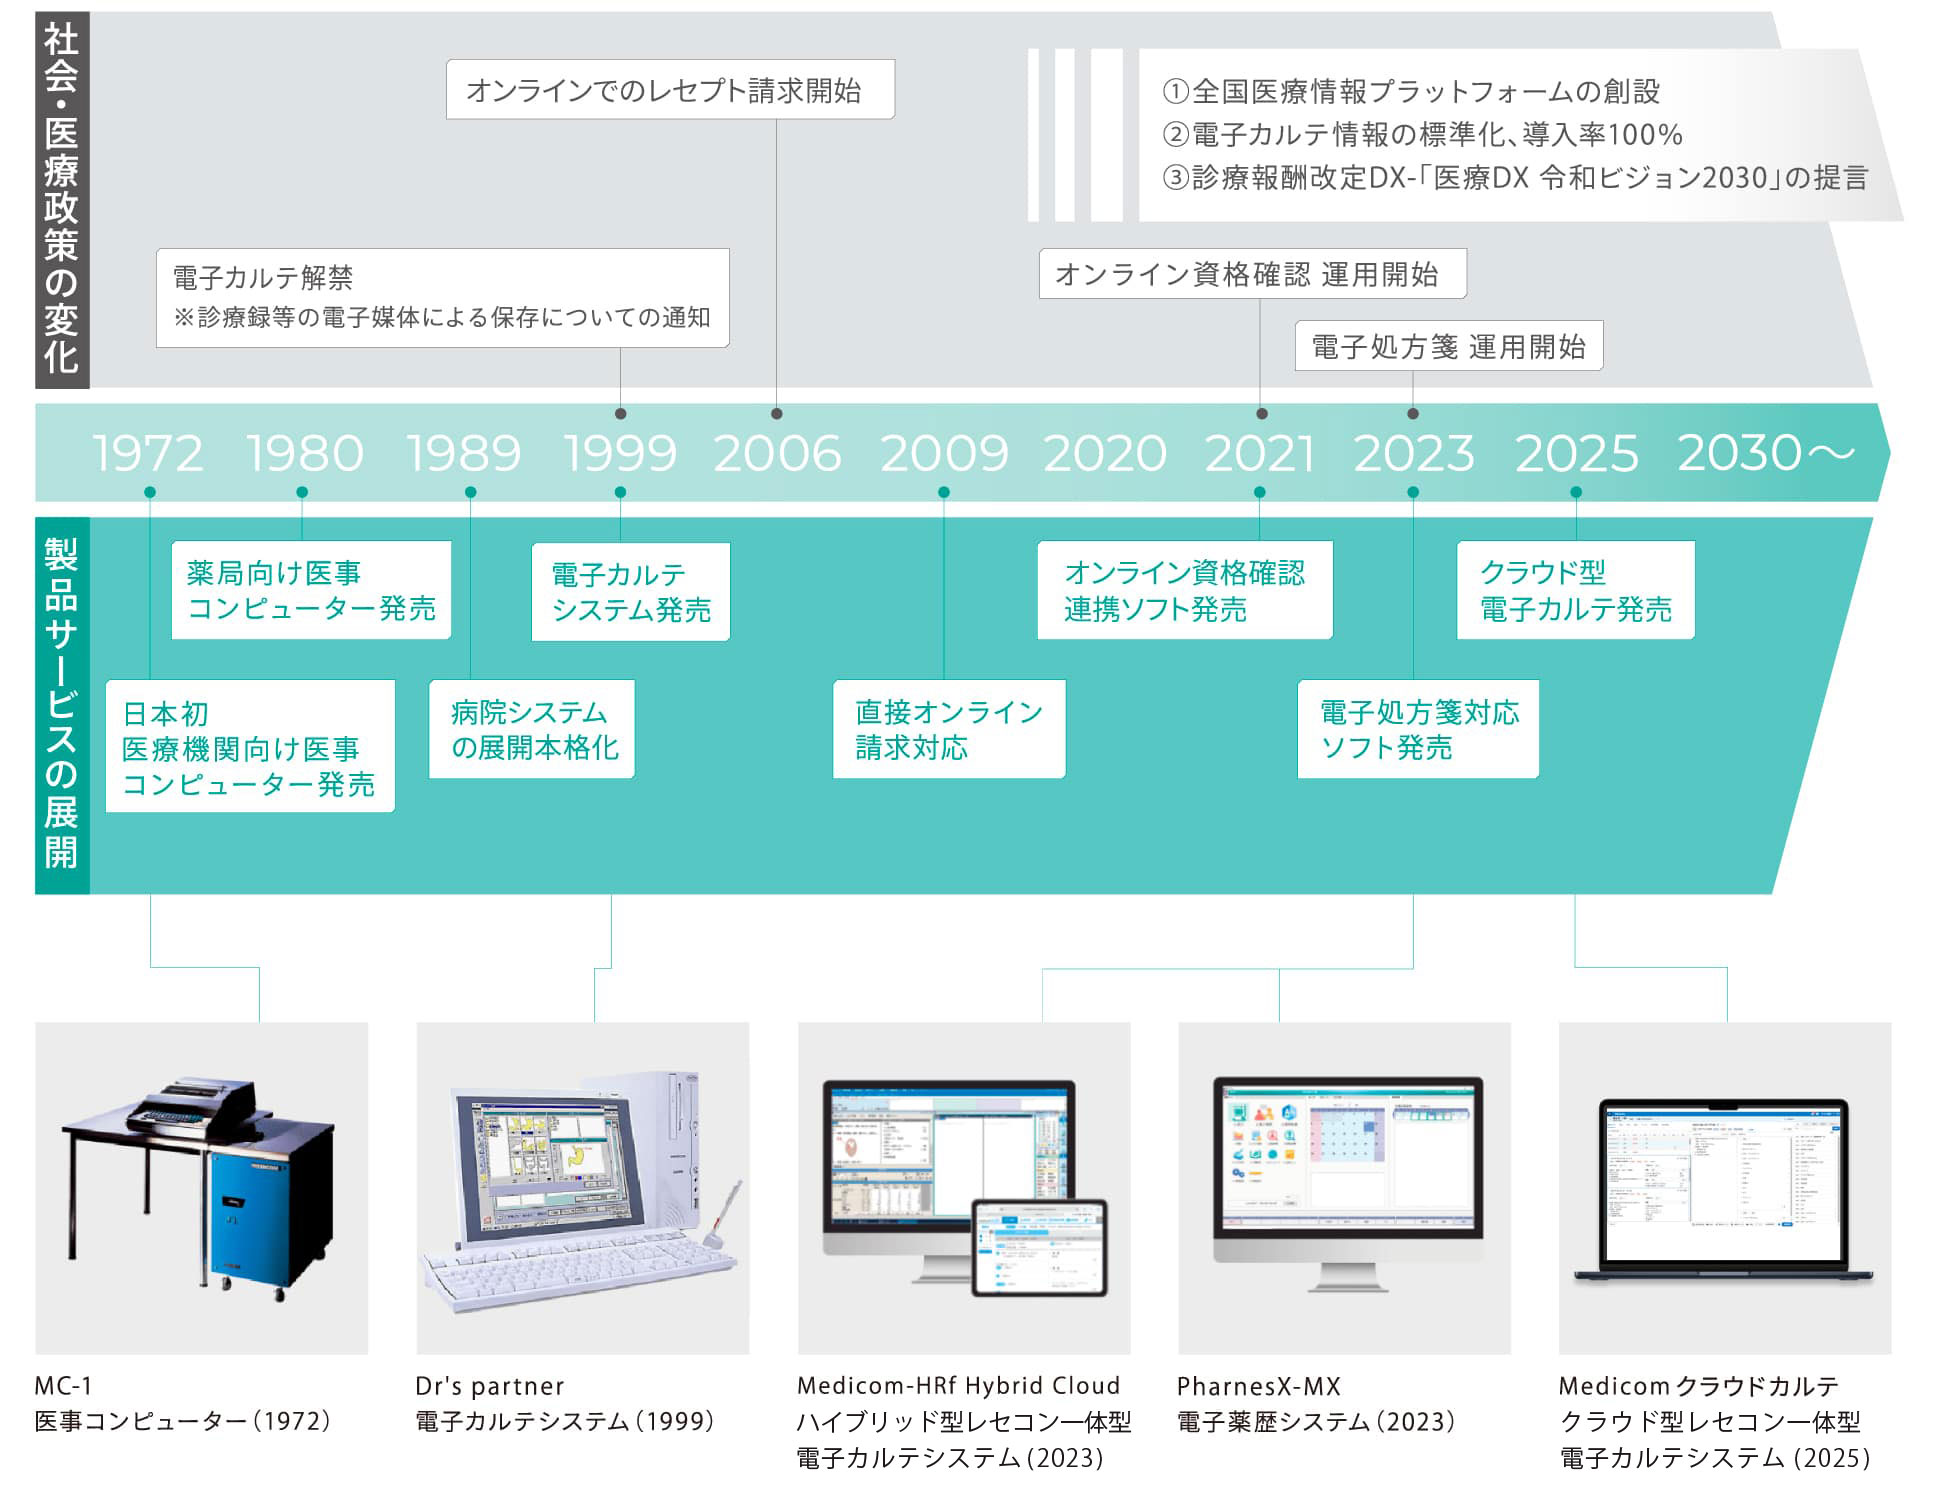

メディコムについて

国策である「地域包括ケア」に沿ったソリューション提供は、長年にわたり医療ITを先導してきたメディコムの責務であると考えます。高齢者が住み慣れた地域で安心して生活できるように、医療・介護・福祉の専門職が協働して適切な支援やサービスを提供する仕組みづくりが求められています。その実現には、医療・介護・健康すべての分野において、情報を利活用できるICTが欠かせません。メディコムは、多職種間をICTでつなぎ、施設医療や在宅医療、介護のシームレスなサービス提供を支援します。